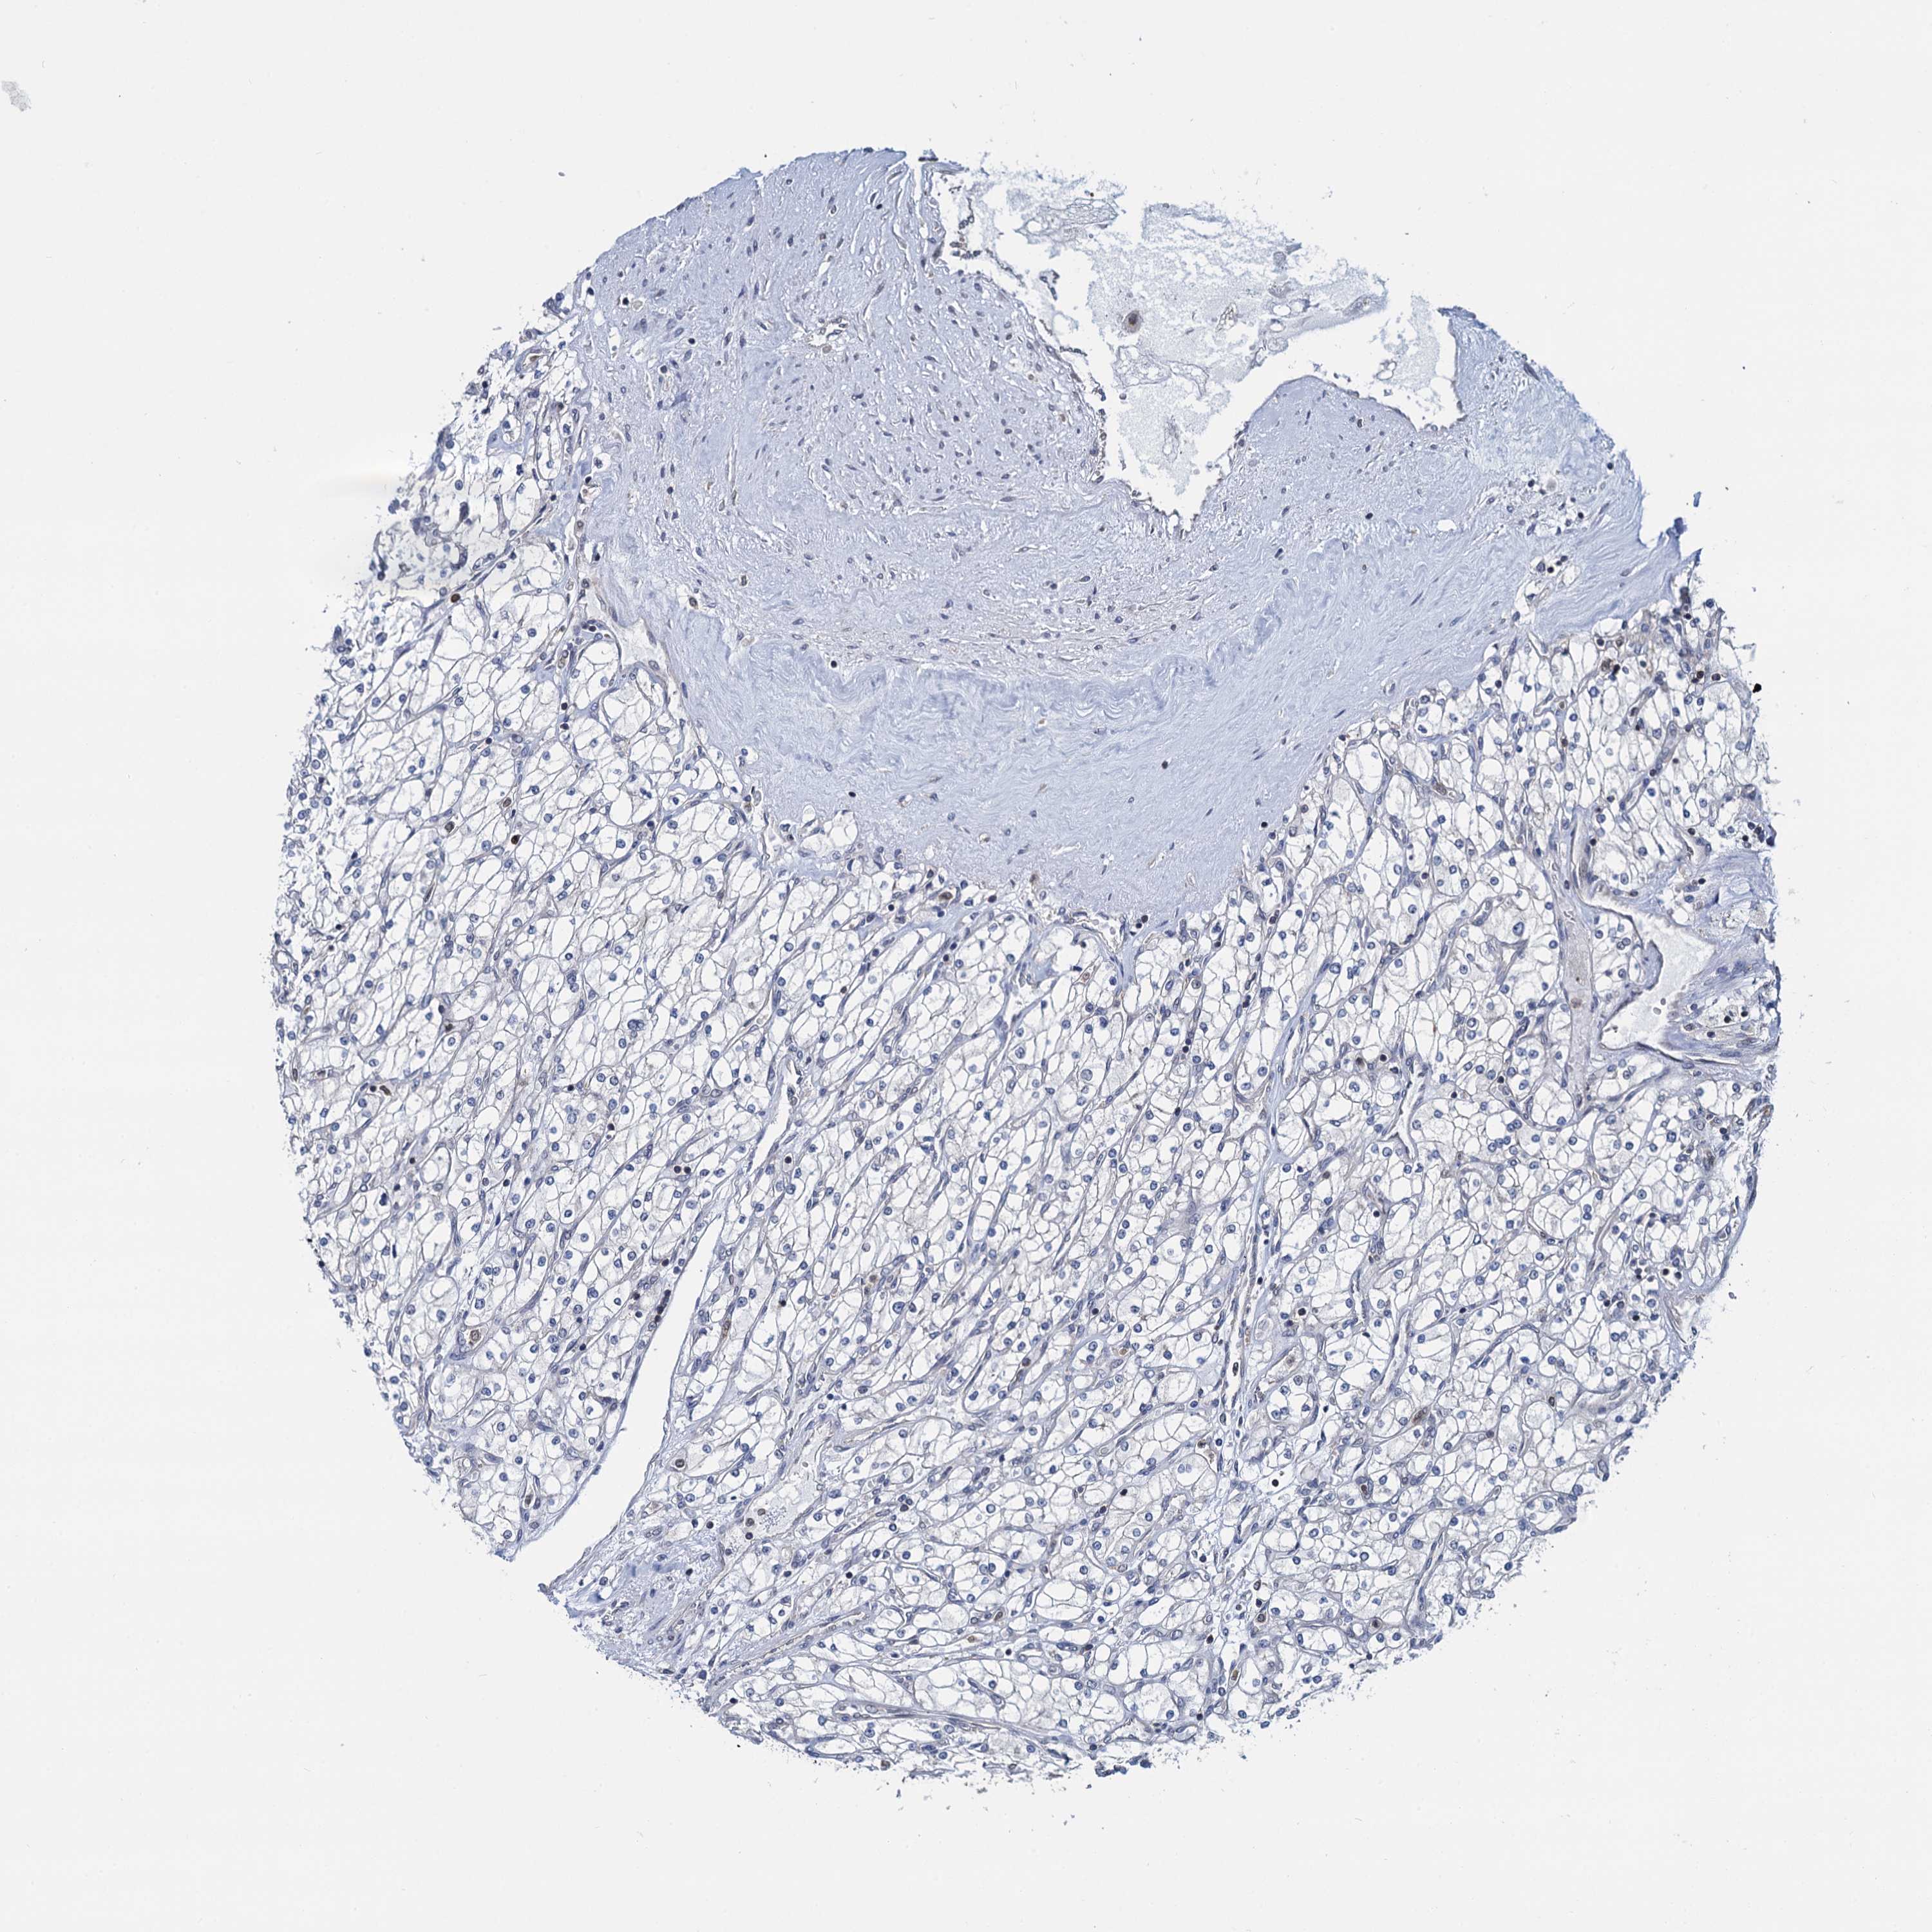

KIDNEY CHROMOPHOBE (TCGA) - Interactive survival scatter ploti

The Survival Scatter plot shows the clinical status (i.e. dead or alive) for all individuals in the patient cohort, based on the same data that underlies the corresponding Kaplan-Meier plots. Patients that are alive at last time for follow-up are shown in blue and patients who have died during the study are shown in red.

The x-axis shows the expression levels (FPKM) of the investigated gene in the tumor tissue at the time of diagnosis. The y-axis shows the follow-up time after diagnosis (years). Both axes are complimented with kernel density curves demonstrating the data density over the axes. The top density plot shows the expression levels (FPKM) distribution among dead (red) and alive patients (blue). The right density plot shows the data density of the survived years of dead patients with high and low expression levels respectively, stratified using the cutoff indicated by the vertical dashed line through the Survival Scatter plot. This cutoff is automatically defined based on the FPKM cutoff that minimizes the p-score. The cutoff can be changed by dragging the vertical line or by entering a cutoff value in the square labeled "Current cut-off".

Under the Survival Scatter plot the p-score landscape (black curve; left axis) is shown together with dead median separation (red curve; right axis). Dead median separation is the difference in median mRNA expression between patients who have died with high and low expression, respectively. It is calculated as follows: median FPKM expression of dead patients with high expression - median FPKM expression of dead patients with low expression. This is intended to aid the user in visually exploring custom cutoffs and the associated p-scores and dead median separation.

Individual patient data is displayed and can be filtered by clicking on one or more of the category buttons on the top of the page. Categories describing expression level and patient information include: high, low, alive, dead, female, male and tumor stages. The scale of the x-axis can be toggled between linear and log-scale by clicking on the "x log" button. Mouse-over function shows TCGA ID, patient information and mRNA expression (FPKM) for each patient.

& Survival analysisi

Kaplan-Meier plots summarize results from analysis of correlation between mRNA expression level and patient survival. Patients were divided based on level of expression into one of the two groups "low" (under cut off) or "high" (over cut off). X-axis shows time for survival (years) and y-axis shows the probability of survival, where 1.0 corresponds to 100 percent.

RNF125 is not prognostic in Kidney Chromophobe (TCGA)

Best expression cut offi

Based on the FPKM value of each gene, patients were classified into two groups and association between prognosis (survival) and gene expression (FPKM) was examined. The best expression cut-off refers the FPKM value that yields maximal difference with regard to survival between the two groups at the lowest log-rank P-value. Best expression cut-off was selected based on survival analysis .

When clicking on this number, the vertical dashed line indicating cut-off, the interactive survival plot, and the Kaplan-Meier curve will be adjusted to show results based on the best expression cut-off.

: 0.37

TCGA RNA samplesi

RNA-seq data is reported as average FPKM (number Fragments Per Kilobase of exon per Million reads), generated by the The Cancer Genome Atlas (TCGA) .

Normal distribution across the dataset is visualized with box plots, shown as median and 25th and 75th percentiles. Points are displayed as outliers if they are above or below 1.5 times the interquartile range. FPKM values of the individual samples are presented next to the box plot.

Average pTPM 1.1

Number of samples 64